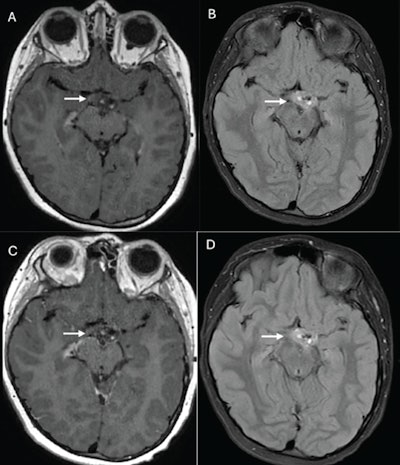

10-year-old boy who underwent brain MRI examinations due to optic tract glioma (A, B) Axial postcontrast 3D T1-weighted fast-spin echo (A) and fluid-attenuated inversion-recovery image or sequence (FLAIR) (B) images from examination performed using gadoterate meglumine. (C, D) Axial postcontrast 3D T1-weighted gradient-recalled echo (C) and FLAIR (D) images from examination performed using gadopiclenol. Images show expansile lesion centered in left optic tract, with punctate enhancement medially and posteriorly (arrow, A-D). Readers 1 and 2 assigned score for border delineation on 3D T1-weighted fast-spin echo of -2 and -1; for border delineation on FLAIR of 0 and 0; for contrast enhancement on 3D T1-weighted fast-spin echo of -2 and -2; for contrast enhancement on FLAIR of 0 and 1; for internal morphology on 3D T1-weighted fast-spin echo of -1 and -2; and for internal morphology on FLAIR of 0 and 0. Negative values indicate preference for gadopiclenol-enhanced examination, whereas positive values indicate preference for gadoterate meglumine-enhanced examination. Image and caption courtesy of the AJR.10-year-old boy who underwent brain MRI examinations due to optic tract glioma (A, B) Axial postcontrast 3D T1-weighted fast-spin echo (A) and fluid-attenuated inversion-recovery image or sequence (FLAIR) (B) images from examination performed using gadoterate meglumine. (C, D) Axial postcontrast 3D T1-weighted gradient-recalled echo (C) and FLAIR (D) images from examination performed using gadopiclenol. Images show expansile lesion centered in left optic tract, with punctate enhancement medially and posteriorly (arrow, A-D). Readers 1 and 2 assigned score for border delineation on 3D T1-weighted fast-spin echo of -2 and -1; for border delineation on FLAIR of 0 and 0; for contrast enhancement on 3D T1-weighted fast-spin echo of -2 and -2; for contrast enhancement on FLAIR of 0 and 1; for internal morphology on 3D T1-weighted fast-spin echo of -1 and -2; and for internal morphology on FLAIR of 0 and 0. Negative values indicate preference for gadopiclenol-enhanced examination, whereas positive values indicate preference for gadoterate meglumine-enhanced examination. Image and caption courtesy of the AJR.